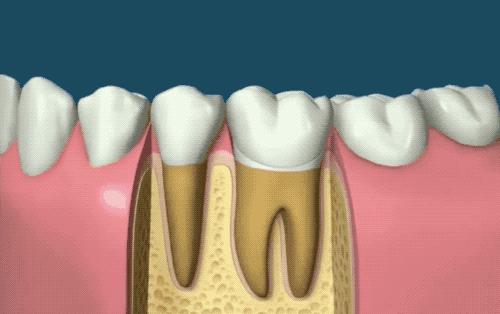

根管治疗俗称「牙齿杀神经」,牙神经就是牙髓。如果因为龋齿或者外伤导致牙髓腔暴露在外,那么细菌会容易侵入牙髓,就是我摔断门牙的那种情况...一旦感染后,就会发展成「牙髓病」或「根尖周病」,就是所谓的疼起来要人命的牙痛了...

先用牙钻在牙齿上钻一个洞,进入牙髓腔。接着牙医根据实际情况选择不同尺寸的钻头将感染的牙本质去除,露出来牙根管(牙医的小钻伴随着呲呲喷溅的凉水,算是我童年最大的噩梦...)